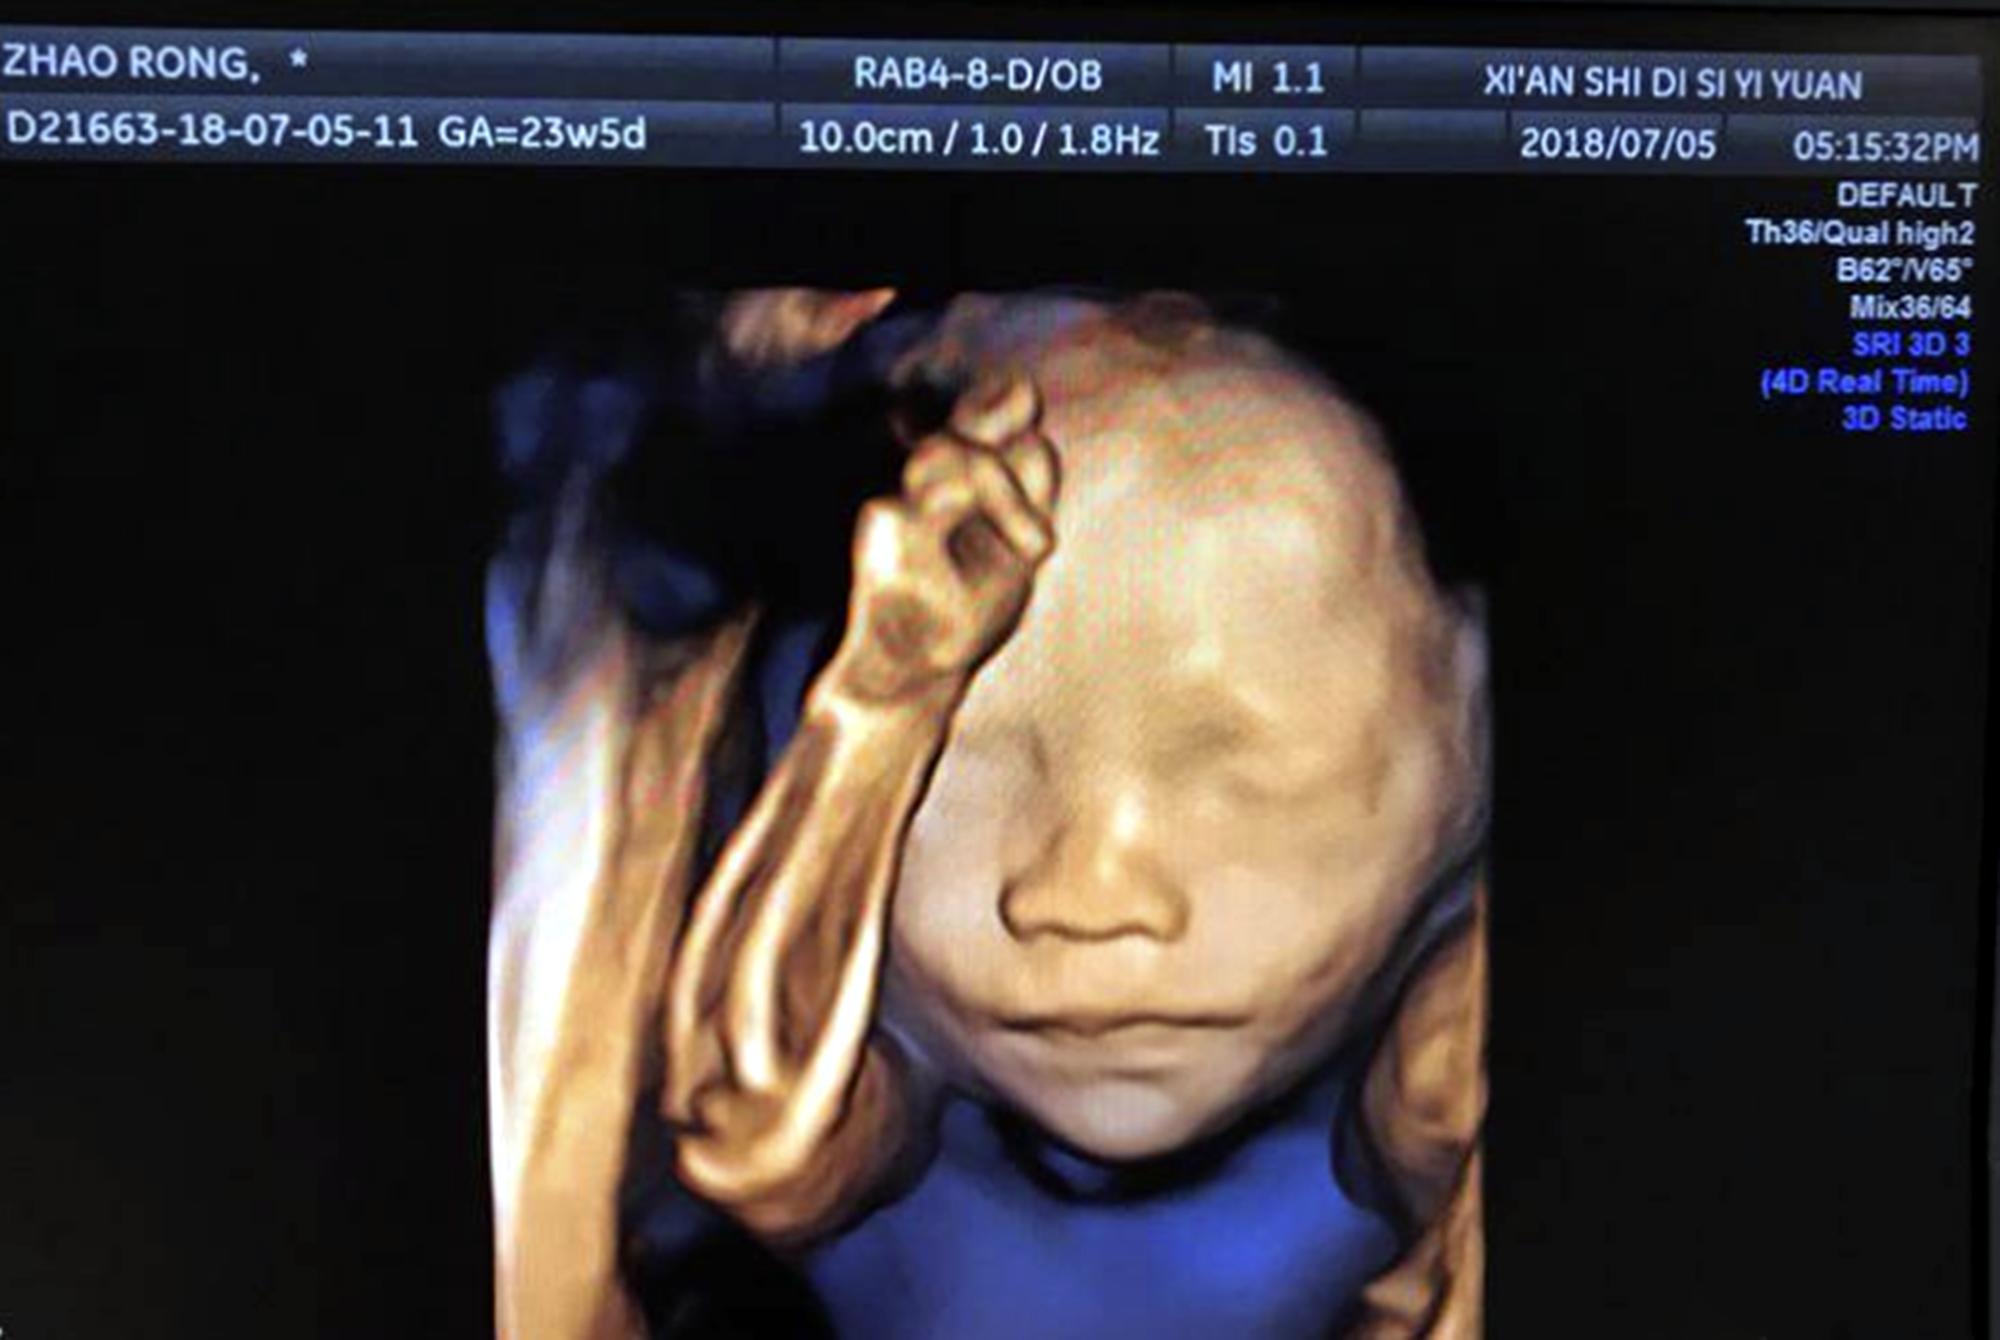

比较典型的案例就是孕检中的四维彩超,这个项目就经常被人吐槽,倒不是它收费昂贵,不合理,而是它的成像技术让人无语。

胎儿四维照“鼻梁塌陷”,宝爸质疑妈妈基因伪劣,出生后却很惊喜

可当四维结果出炉后,看着胎宝宝的“彩超照”,小陈却皱了眉:照片里胎儿的样貌看着很一般,尤其鼻子好似塌陷一般,不随妈妈也不随爸爸。

很多宝妈都反映过,她们说四维彩超的成像结果与现实存在很大区别,它就像是“美图秀秀”的“负面版本”,专门把胎儿往丑里拍。

四维彩超技术,是利用超声波的反射效应,搭配专业的数据转变软件,实时获取胎儿三维图像的技术。

与三维超声技术最大的区别在于,它多了一个时间轴,也就是说,最终检查结果是以录像的形式呈现的,而并非三维超声技术的图片。

孕妈之所以要做四维彩超,目的在于监测胎儿面部、心脏、四肢等全身发育情况,还可以分析羊水的数量以及质量,以便发现有异常后及时采取措施治疗。四维彩超的目的是排畸,检查宝宝的发育情况,不是让大家看宝宝长得啥模样,很多妈妈都搞混了。

尽管四维彩超技术号称是世界上目前最先进的彩色超声成像技术,但行内人都知道,其效果并没有吹嘘的那么夸张。

不论是颜色、轮廓塑形以及图像稳定性,它都存在不小问题,我们只能说,与过去的技术相比,它无疑是非常先进的,但是离完美还有不小的距离。

既然技术尚且存在缺陷,那检查结果出现偏差,也是情理之中的事情,大家千万不要简单地将四维彩超结果当成现实,二者不能划等号。